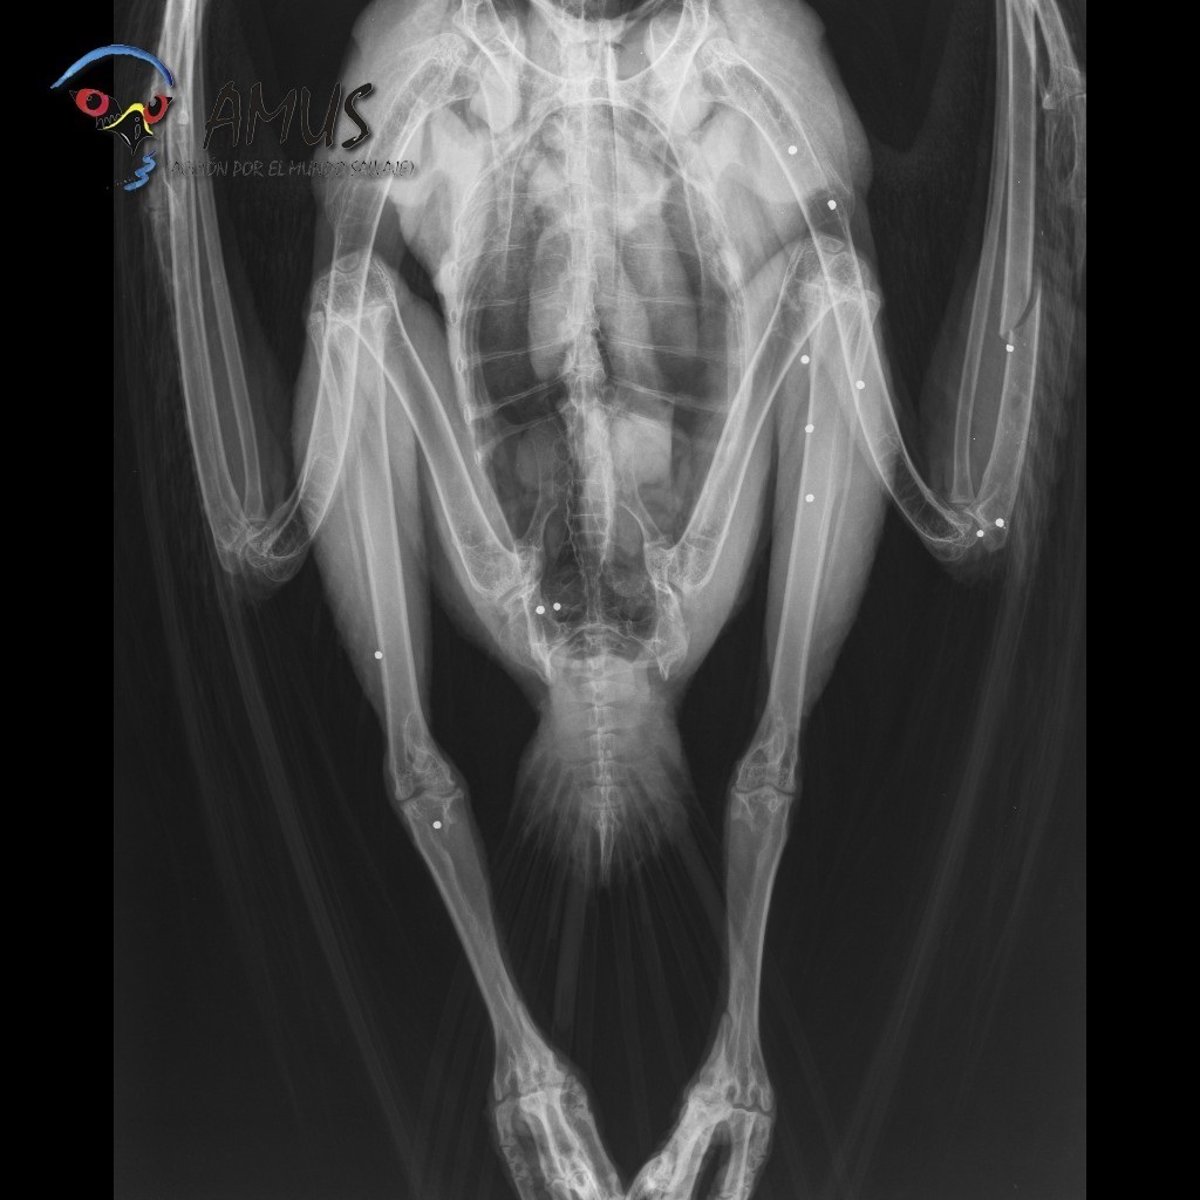

La organización animal AMUS ha conseguido recuperar, tras tres meses de cuidado, a un águila real que fue ingresada en su hospital al ser disparada en la Campiña sur de Extremadura.

Dicho animal fue recogido por un Agente del Medio Natural y del cuerpo del Seprona de la Guardia civil en la zona del Hotel Mirador de Azuaga (Badajoz) "con una grave fractura en un ala provocada por el disparo".